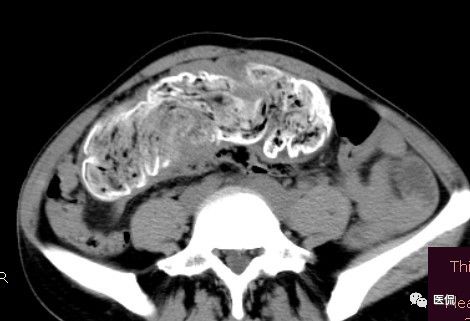

腹腔内残留的纱布在人体内引起渗出或液化坏死并纤维包裹形成异物性脓肿(纱布瘤)。纱布瘤的影像特点:圆形或卵圆形肿块,较大,有完整包膜,薄壁,较少的情况下为厚壁,边界较完整,增强后薄膜可以持续强化。不同时期的纱布瘤可以有不同表现:早期(10个月或半年内)多表现为蜂窝状;2~5年内一般表现为囊性飘带状;10~20年之后则为实性软组织密度,包膜钙化呈钙化网状结构。手术过程中残留在人体内的医用纱布所形成的肿瘤样病变。

腹腔内遗留纱布团的影像学表现,以B超较具特征性,其主要表现为:腹腔或盆腔内特殊率减的黑色包块,后方伴有扇形衰减的声影,上窄下宽,好似一“黑色大布”,早期包块内含有不规则光团或光点,随时间延长有缩小或消失,为纱布团内气体。CT的优势在于早期常表现为软组织密度的肿块,其内可见多少不等的气泡,随时间的延长气泡逐渐被吸收减少至消失,增强扫描可见包膜不同程度强化而内容物无强化。熟悉其影像学表现,可在术前作出明确诊断。